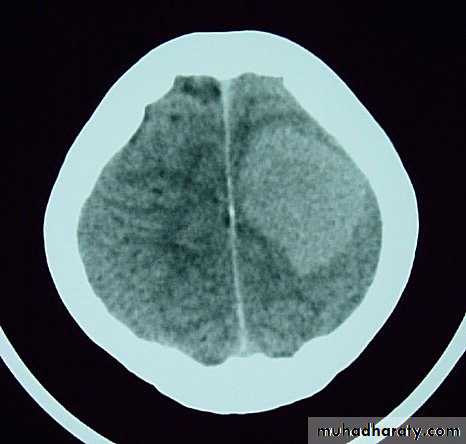

Metastatic Brain TumoursMRI